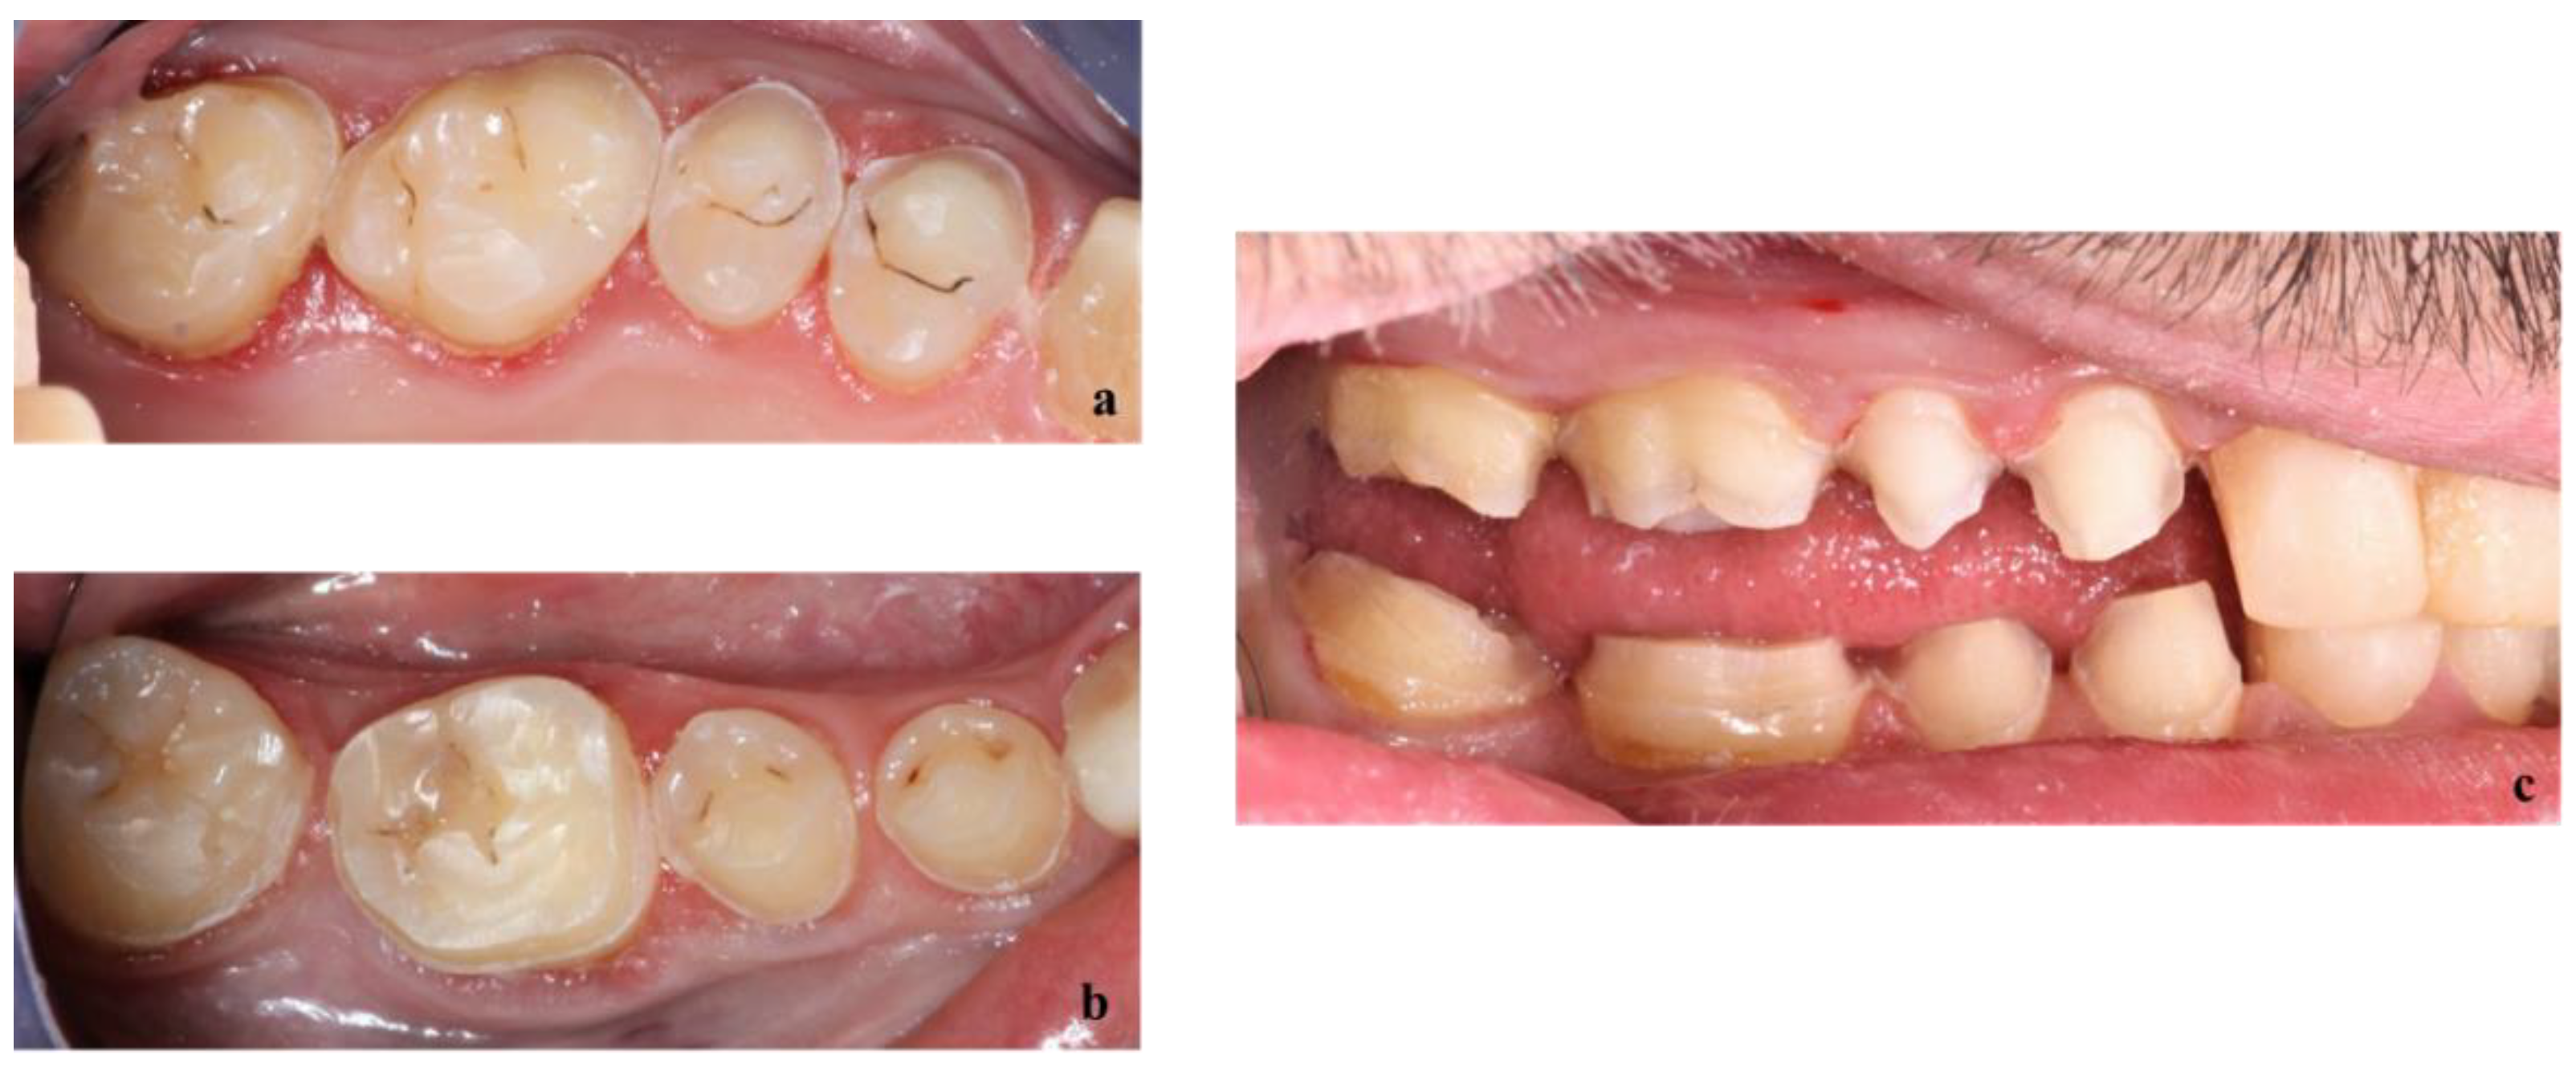

First, alginate impressions were made to obtain diagnostic casts. These casts were mounted in an articulator in order to analyze the case. Face photos and intraoral views were taken and are presented in Figure 1 and Figure 2. The orthopantomogram shown in Figure 3 was realized.

Figure 2.

Endobuccal views: (a) maxillary arch, (b) mandibular arch, (c) right side occlusion, (d) front bite, (e) left side occlusion.

Exobuccal clinical assessment showed a leftward convergence of the facial lines, an asymmetric smile, and the presence of oral corridors. The profile examination showed a lowering of the lower face, an open naso-labial angle, a concave subnasal profile with a reduced cervical-chin distance and a biretrochelia.

Endobuccal clinical assessment revealed dental agenesis of the upper left and right lateral incisors and lower left and right central incisors, generalized small teeth size, infiltrated maxillary grooves, and an amalgam restoration on the occlusal surface of the lower left second molar. Occlusal analysis showed complete overbite, a left unilateral articular inversion on the two upper left molars, an Angle Class I canine and molar on the right side and an Angle Class II canine and molar on the left side. In addition, the anterior overhang is reduced, so the patient is in class II division 2.